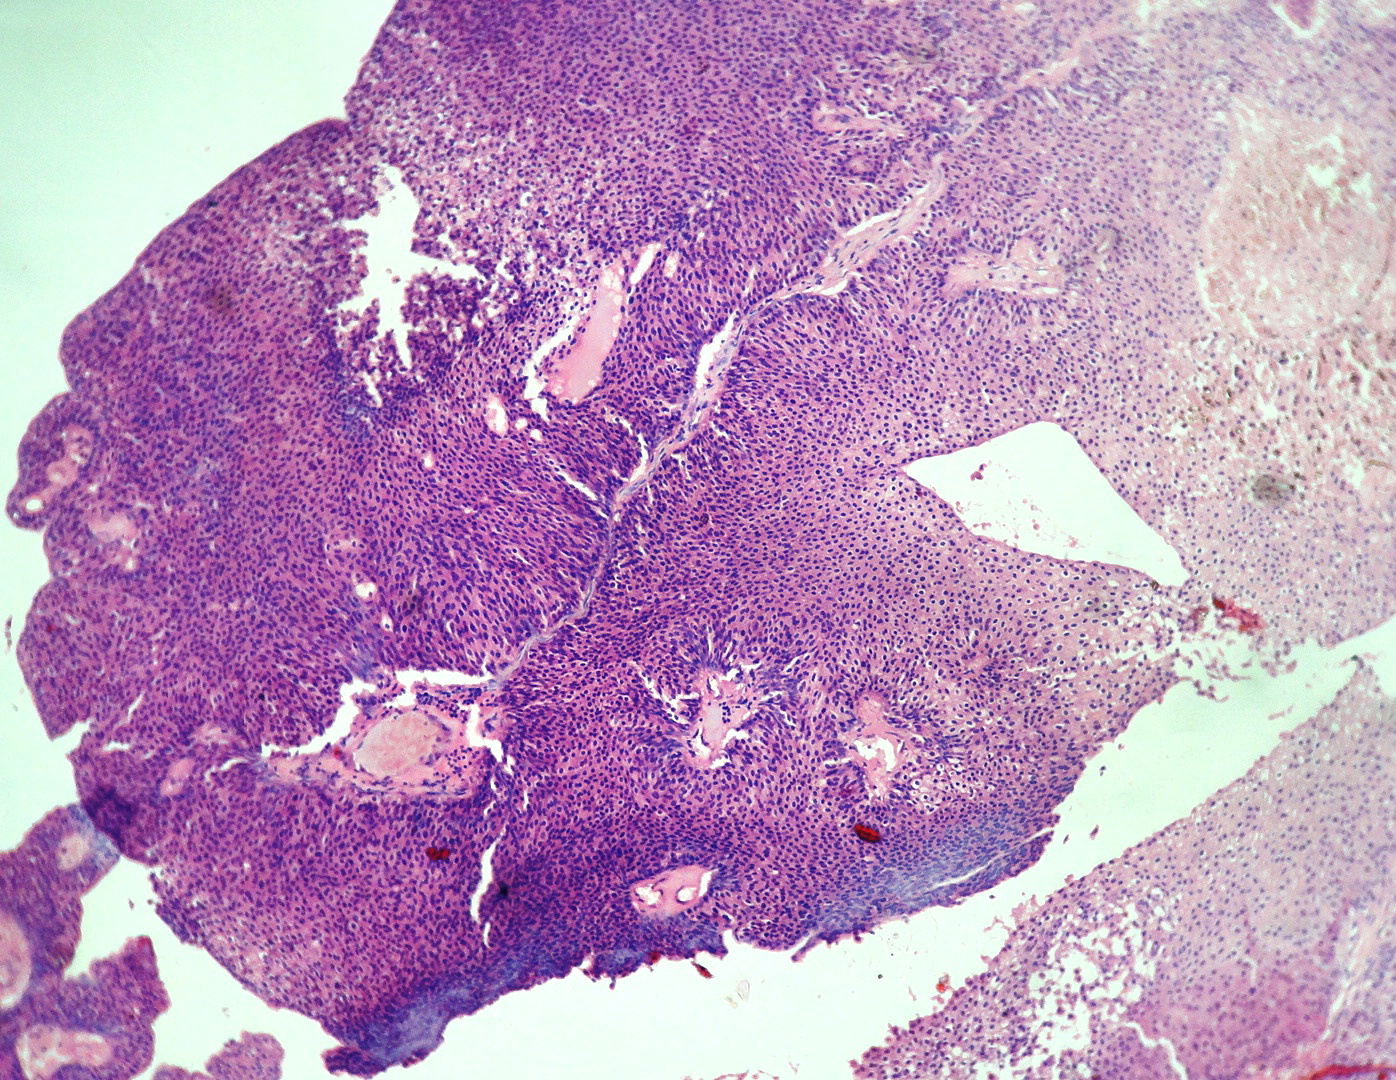

In our study, we made an attempt to evaluate the pattern of tumor growth, its degree of differentiation, progression and associated mucosal changes. In 15 cases of urothelial papilloma, it is characterized by discrete papillary growth with a central fibrovasular core lined by urothelium of normal thickness and cytology (Figure 1). In five cases of Papillary urothelial neoplasm of low grade malignant potential (PUNLMP), histopathologically the tumor is characterized by delicate, orderly, tenuous papillary structures with orderly arrangement of cells within the papillae with minimal architectural abnormalities and nuclear atypia usually limited to basal layer irrespective of cell thickness (Figure 2). The major distinction from papilloma is that in PUNLMP the urothelium is much thicker and nuclei are significantly enlarged. In 21 cases of low grade urothelial carcinoma, histologically it is characterized with papillary axes which are more compact, crowded, fused at the base and lined by unordered cells showing both architectural and cytological abnormalities with frequent mitosis (Figure 3). In 51 cases of high grade urothelial carcinoma showed fused papillary axes over the large areas resulting in sheets and solid areas. The cells have enlarged, hyperchromatic, pleomorphic nucleus in full thickness of the epithelium with increased atypical mitosis (Figure 4). As per TNM staging used in our study we observed majority of the bladder tumours were invasive accounting for 78.25% (Figure 5 & 6) as compared to non-invasive bladder tumours constituting 21.73% of the cases as shown in table 3.